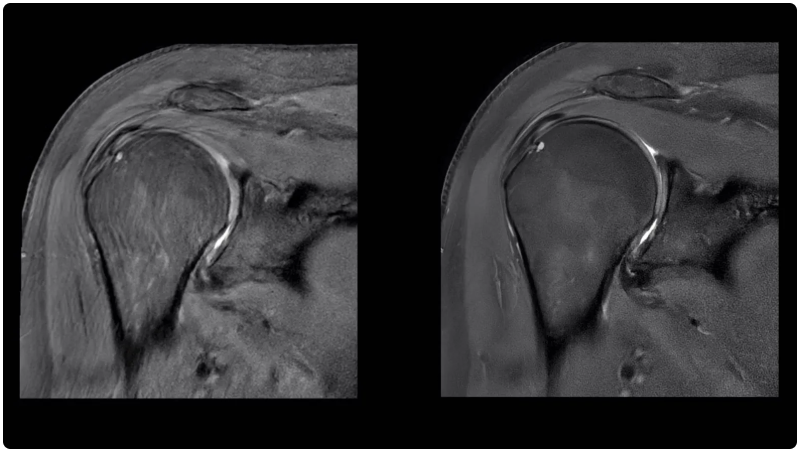

肩部掃描圖像(左)與使用人工智能功能銳化后的相同圖像(右)進(jìn)行對(duì)比。Air Recon DL 是通用電氣醫(yī)療集團(tuán)的旗艦人工智能產(chǎn)品之一,旨在提高圖像質(zhì)量,縮短核磁共振成像掃描時(shí)間。

自2022年MedTech Dive首次分析FDA數(shù)據(jù)以來(lái),通用電氣醫(yī)療集團(tuán)(GE Healthcare)和西門(mén)子醫(yī)療集團(tuán)(Siemens Healthineers)的人工智能設(shè)備數(shù)量位居榜首。截至2024年8月7日,通用電氣醫(yī)療集團(tuán)共有81臺(tái)人工智能設(shè)備獲得授權(quán)。其旗艦人工智能產(chǎn)品之一 Air Recon DL 于 2020 年推出。通用電氣醫(yī)療保健公司的人工智能宣傳負(fù)責(zé)人Jan Beger說(shuō),這種算法可以提高圖像質(zhì)量,并將核磁共振掃描時(shí)間最多縮短50%。截至 2024 年 10 月,該公司已使用該軟件掃描了 3400 多萬(wàn)名患者。Beger 將通用電氣醫(yī)療保健公司的人工智能方法分為三類(lèi):用于提高成像效率的 Air Recon DL 等產(chǎn)品、從各種來(lái)源提取數(shù)據(jù)以幫助臨床醫(yī)生做出決策的人工智能以及用于規(guī)劃的企業(yè)級(jí)系統(tǒng)。有時(shí),這些功能內(nèi)置在公司銷(xiāo)售的成像設(shè)備中。在其他情況下,通用電氣醫(yī)療保健公司會(huì)將這些功能作為單獨(dú)的訂購(gòu)產(chǎn)品出售。“總的來(lái)說(shuō),人工智能的理念其實(shí)是,我們?nèi)绾尾拍軐⑷哂?、重?fù)、平凡的任務(wù)自動(dòng)化?”Beger說(shuō)。